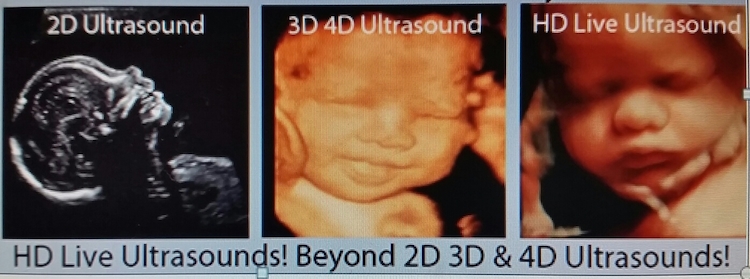

4D agrega la “dimensión del tiempo” a la ecuación, también conocida como tiempo real. La ecografía 5D es actualmente la ecografía más nueva y avanzada que existe. También se conoce comúnmente como HD Live. 5D y HD Live tiene una resolución superior y parece una imagen de ultrasonido 3D/4D más realista.

4D agrega la “dimensión del tiempo” a la ecuación, también conocida como tiempo real. La ecografía 5D es actualmente la ecografía más nueva y avanzada que existe. También se conoce comúnmente como HD Live. 5D y HD Live tiene una resolución superior y parece una imagen de ultrasonido 3D/4D más realista.

Como el avance más reciente en tecnología de ultrasonido, los ultrasonidos HD y HD Live (también llamados 5D) nos permiten capturar imágenes aún más claras y nítidas. Estas imágenes están más definidas y tienen mejor resolución.

Los escaneos 2D capturan imágenes axiales, 3D se basa en la recopilación de datos de volumen, 4D combina escaneos de tiempo y volumen, mientras que 5D cambial flujo de trabajo para intentar automatizar el proceso con la máxima eficiencia. La tecnología de ultrasonido 5D tiene como objetivo hacer que el proceso consuma menos tiempo al completar automáticamente los resultados después de un escaneo.